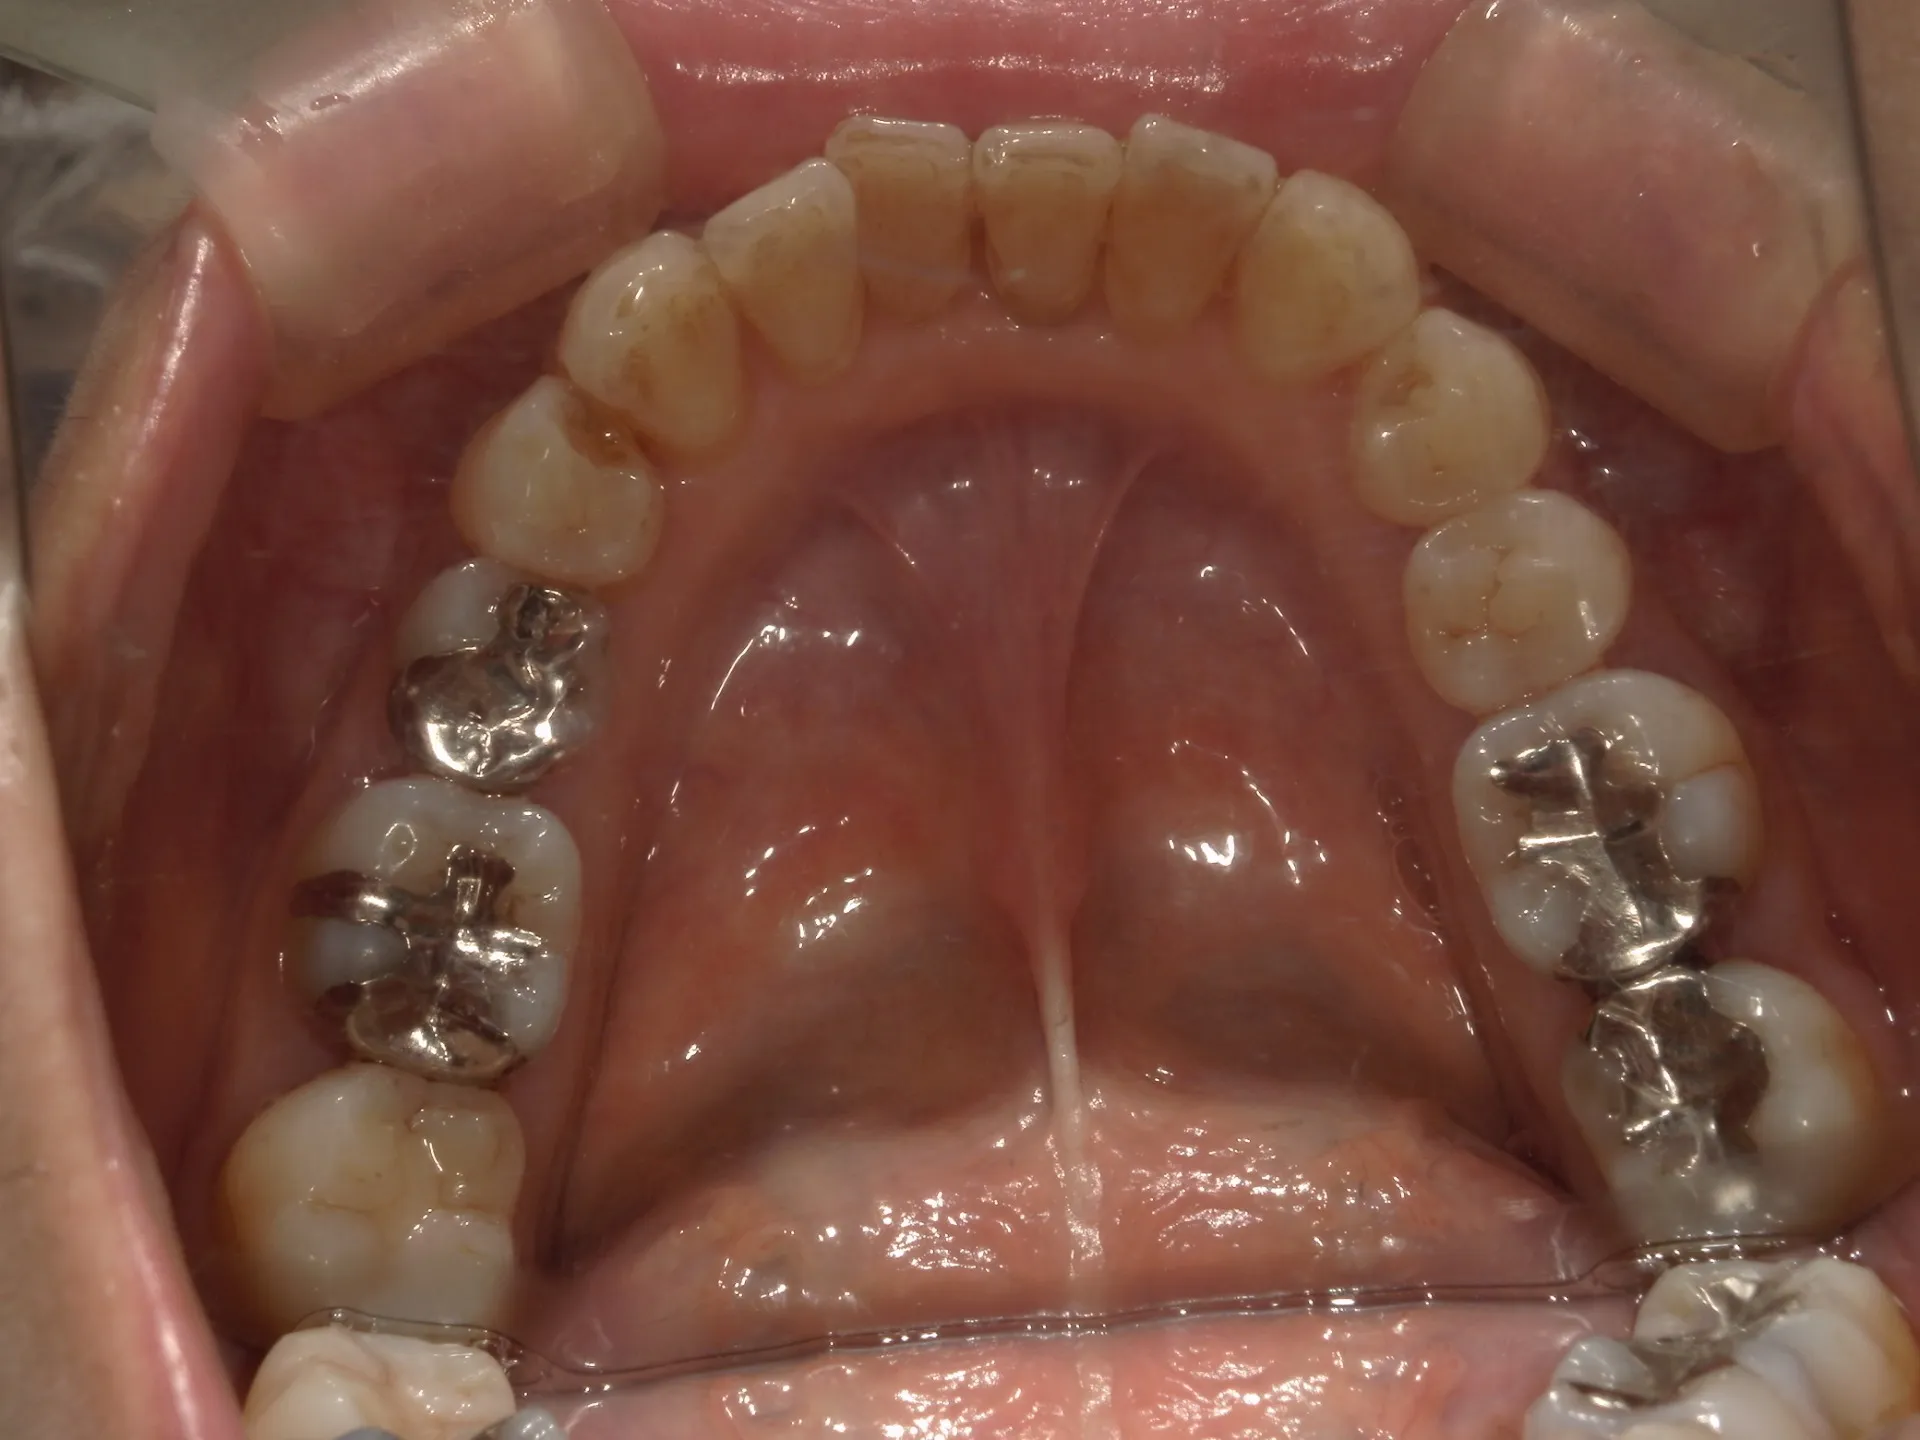

当院では矯正治療と歯周治療を平行して行うことにより矯正治療を進めていけることができました。

しかしながら、今回の治療途中で歯茎が腫れるなどの影響もあり、歯周治療中の矯正治療はリスクであることは患者様にも初回の段階で説明していることもあり、患者様もこの状態の歯並びで満足しており、歯を残すためにも今回は矯正治療を中断する希望をされました。